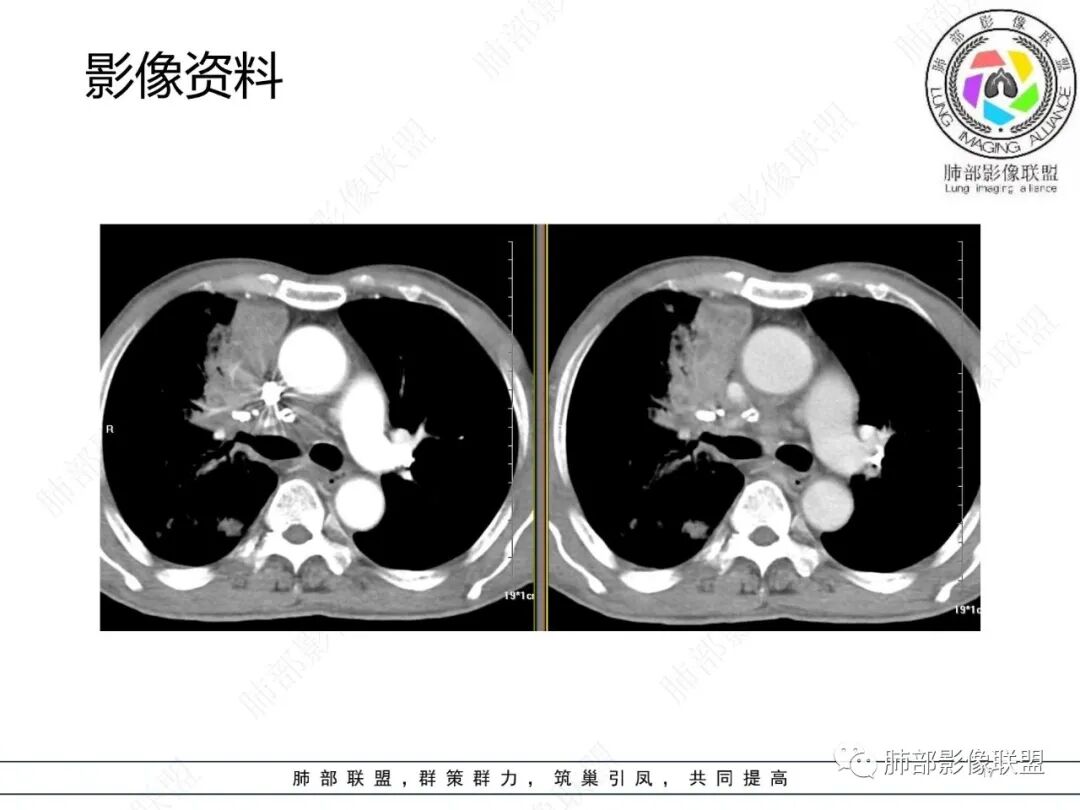

影像资料

2.胸部CT: 右肺病灶,主要累及右肺上叶前段、右肺中叶内侧段及右肺下叶背段,片状影及结节影,实性密度为主,部分磨玻璃晕,密度不均,散在钙化,其中上叶前段支气管闭塞,隐约见钙化突入。未见明确“硬树芽”或“拐枣征”。主要呈延迟强化,其间低密度区疑坏死或粘液成分。纵隔内见多组淋巴结肿大环形强化,部分钙化。

3.综合分析:影像病灶集聚(右肺上叶前段、右肺中叶内侧段),实性密度为主,钙化及液性密度区,淋巴结环形强化等,较常见于继发性肺结核,或伴其他混合感染(支气管阻塞)。尽管未见典型硬树芽。